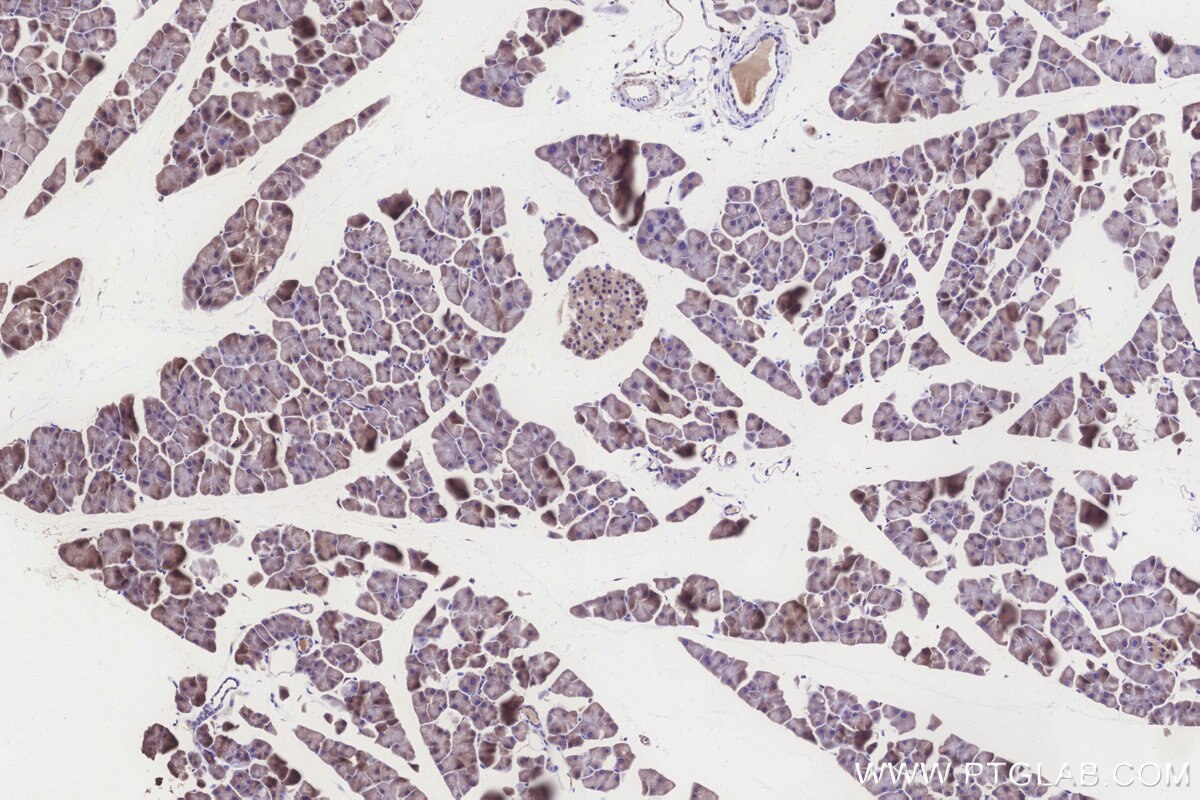

Validation Data Gallery

KHC3260 is a ready-to-use IHC kit for staining of ALDH1L2. The kit provides all reagents, from antigen retrieval to cover slip mounting, that require little to no diluting or handling prior to use. Simply apply the reagents to your sample slide according to the protocol and you're steps away from obtaining high-quality IHC data.